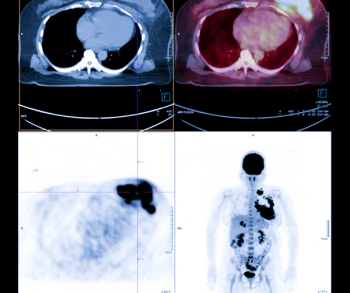

A recent prospective study found that progression-free survival (PFS) and disease-specific survival (DSS) were significantly associated with breast cancer tumor treatment response on 2-(18F)FDG-PET/CT imaging in comparison to contrast-enhanced computed tomography (CT), which showed no evidence of a significant association with tumor response.